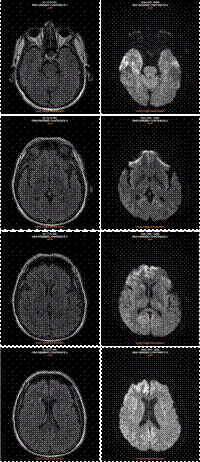

On day 3 of admission the patient presented neurological decline with dysphagia, recurrent myoclonic jerks at night time, and behavioral impairments such as aggression, psychomotor agitation and incomprehensible language. A new MRI of the brain revealed an increase on the hyperintense areas on DWI (Figure 1) ruling out neoplastic, ischemic or bleeding processes. A few days later, consciousness began to deteriorate and an EEG revealed a NCSE with moderate encephalopathy, delta/theta triphasic activity and a symmetric fluctuating frequency of 2.5 Hz throughout the reading (Figure 2). These findings were considered suggestive of sporadic onset prionopathy, and the patient was started on valproic acid 1000 mg initial dose, then 500 mg every 8 hours. Later it was necessary to add therapy with levetiracetam 1000 mg every 8 hours. Other causes of encephalopathy were taken into consideration, such as paraneoplastic syndrome and autoimmune encephalitis, for which a contrast tomography of the chest and abdomen were performed with normal results, and a therapeutic test of intravenous pulsed methylprednisolone 1000 mg every 24 hours for 5 days was initiated, with no neurological improvement. A new EEG was performed 8 days after the first one without significant changes compared to the initial one, with persistence of delta/theta activity of triphasic morphology with a frequency of 2.5 Hz symmetrical that increases and decreases along the route, compatible with NCSE.

Figure 1 MRI of the brain with flair (left) and diffusion (right) weighted images revealing hyperintensities on the upper left parasagittal frontoparietal cortex, right head of caudate nucleus, and on the right side of the anterolateral and upper frontal temporal occipital cortex.